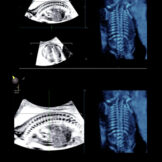

La caratteristica della tecnologia tridimensionale consiste nel fatto che non si lavora su un piano ma su un volume. Pertanto è possibile non solo, esaminare un determinato distretto nelle tre dimensioni, ma di manipolare sui tre piani il volume immagazzinato, consentendo di mettere in evidenza strutture anatomiche altrimenti difficilmente evidenziabili. Pertanto il 3D e il 4D non viene utilizzato esclusivamente per visualizzare il visino del feto* e le parti superficiali come le mani e i piedi ma per studiare il cervello (neurosonografia)**, l’apparato scheletrico *** e quello cardiocircolatorio****.